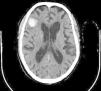

There is evidence that uremic environment and glomerular filtration rate decline in patients with chronic kidney disease, aggravate cognitive functions and are related to microhemorrhages occurrence.6 Both, it is necessary to clarify to what extent anticoagulant or antiplatelet treatments worsen CAA evolution. In this regard, it is interesting the case of an 82 years old patient with chronic kidney disease and hemodialysis for four years, who was evaluated due to a 48hours disorientation state. His antecedents included memory impairment for nine years and an episode of multiple microangiopathic infarcts eight years ago. Non-contrast head CT showed a right frontal hematoma with perilesional edema, and hypodense lesions located in periventricular and subcortical white matter and left cerebellar hemisphere. That supported former infarcts or hemorrhages. According to the Boston criteria,7 the patient diagnosis was probable CAA.

The deficiency of standardized strategies to detect CAA and the bleeding risk that the disease entails, complicate the management of concomitant pathologies with antithrombotic therapy requirement. This is particularly important in patients under hemodialysis, who need anticoagulation treatment during sessions. In regard to antiplatelet treatment, retrospective researches show different outcomes respecting bleeding risk,8 although acetylsalicylic acid is generally avoided and replaced by clopidogrel. Anticoagulation with heparin is also controversial. On the one hand, a case report of CAA-related inflammation treated with enoxaparin 4000IU/12h due to venous thrombosis, described a subsequent big cerebral hematoma which caused death.9 On the other hand, low-molecular-weight heparin (LMWH) is recommended despite cerebral hemorrhage if immobilization extends beyond 3–4 days.10 In the exposed case of the patient, LMWH treatment was kept during hemodialysis sessions, and he continued his previous therapy with clopidogrel. Six days later, a control non-contrast head TC showed the resolution of acute hemorrhage, and due to the remarkable clinical improvement, the patient was discharged from the hospital showing a normal orientation state (Figs. 1 and 2).